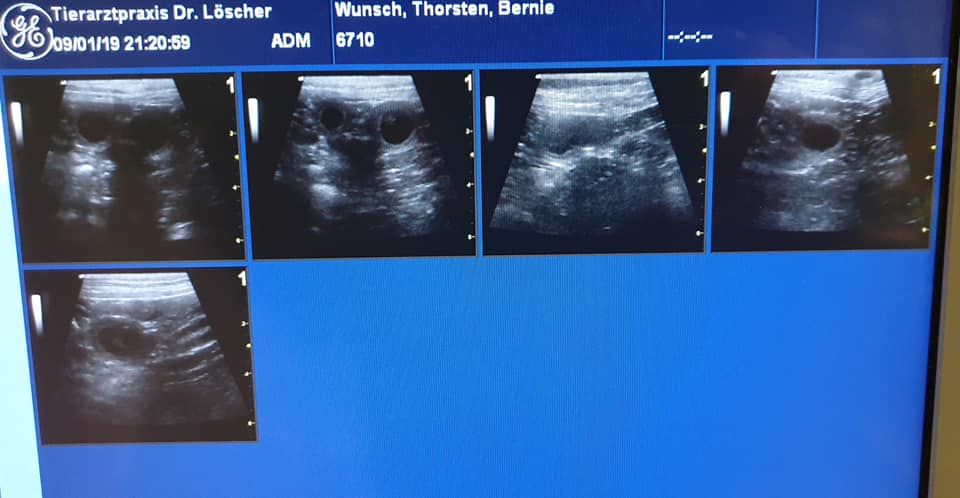

6 Wochen alt - Fotoshooting mit Micha & Maddy4 Wochen alt2 Wochen alt1 Woche altErste Eindrücke 14.04.2019 Thorsten 14.04.2019 ThorstenDie ElternUnsere Berny -mit einem Klick zu Bernies Seite- (Fairy Floss' Dr. Bernadette Maryann Rostenkowski-Wolowitz) & Strolch (Meadow Valley's It Wasn't Me) werden, wenn alles nach Plan verläuft Mitte Februar 2019 Welpen bekommen.Update 2019-01-09: Bernie bekommt Babies! Der Ultraschall hat vitale Anlagen gezeigt. Wir freuen uns!   Wenn ihr Interesse an einem tollen Begleiter habt, freuen wir uns auf euer Kontaktformular... KONTAKT  17.02.2019 Thorsten 17.02.2019 Thorsten